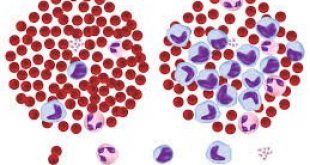

Στην ίδια μελέτη, υπολογίστηκε και η διάμετρος των αγγείων, όταν οι συμμετέχοντες είχαν κληθεί να παρακολουθήσουν ένα βίντεο που θεωρείτο αστείο και ένα που προκαλούσε άγχος. Οι διαφορές ως προς την διάμετρο των αγγείων ξεπερνούσαν το 30% με 40%.

Αξίζει να αναφερθεί ότι το ενδοθήλιο, η εσωτερική επιφάνεια των αγγείων, είναι το πρώτο που επηρεάζεται κατά την σκλήρυνση του αγγείου και αποτελεί την απαρχή της καρδιαγγειακής νόσου.